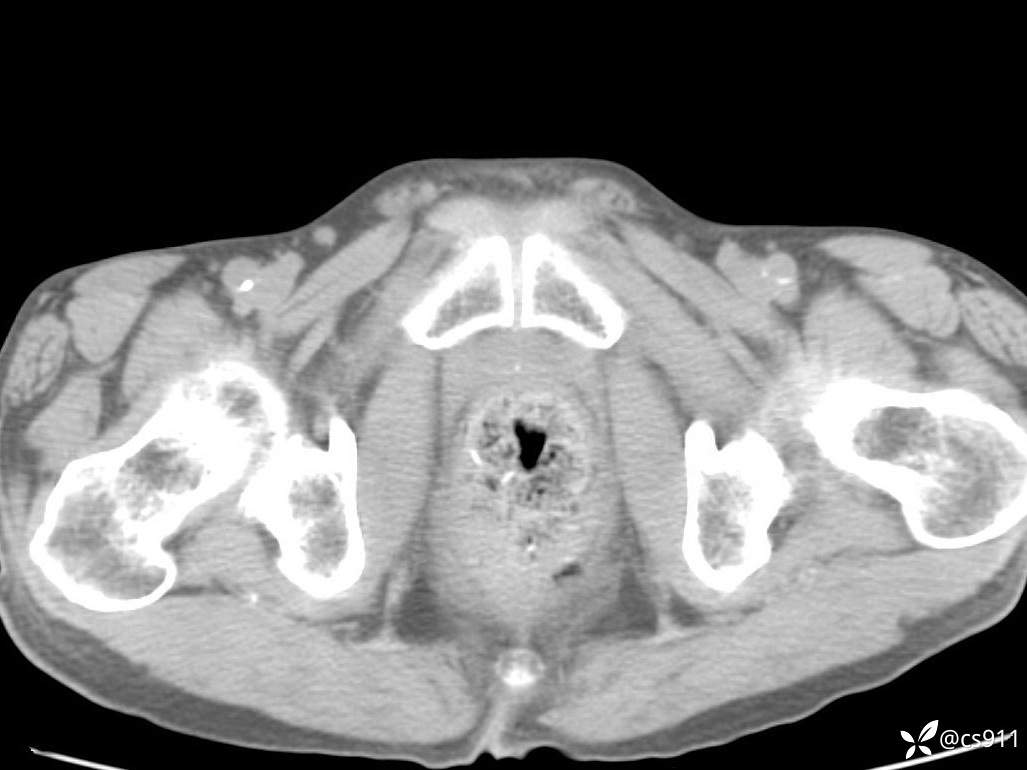

急腹症之急诊CT,原因?答案公布

男,77岁,腹痛、腹胀伴恶心呕吐1天。呕吐胃内容物,非喷射性呕吐,有咖啡色样胃内容物,诉有胃穿孔病史。查体:全腹平,下腹部压痛,全腹无反跳痛,叩诊呈浊音,移动性浊音阴性,肠鸣音减弱,1-2次/分。肛检:直肠未扪及明显肿物,可触及大量粪块。

T 36.6℃ P 80次/分 R 26次/分 BP 100/60mmHg

白细胞(WBC) H 14.55 10e9/L 4-10

中性粒细胞百分率(NEUT%) H 85.7 % 40-75

血淀粉酶(AMY) HH 1859 U/L 35-135

癌胚抗原(CEA) H 27.44 ng/ml 0-5

呕吐物 潜血试验 * 阳性 阴性

患者轮椅入室检查神志清楚, 能配合摆位和呼吸